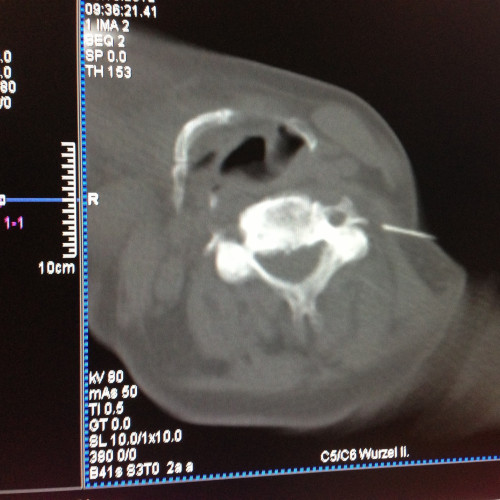

CT-gezielte Infiltrationsbehandlung – Es kann die Nadel millimetergenau an die betroffene Region gebracht werden. Die Strahlenbelastung ist in etwa gleich der röntgengezielten Infiltration mit dem Vorteil der besseren Darstellung der Strukturen. Die CT-gezielte Infiltration wird von mir im Röntgeninstitut „Bellaria Diagnose“ im ersten Wiener Bezirk ambulant durchgeführt.